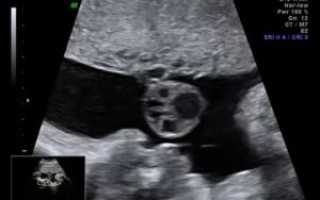

При этом, эхографически подобные аномалии являются анэхогенными образованиями, которые находятся в структуре пуповины, при этом, не нанося вреда ходу кровеносных сосудов.

При ультразвуковом обследовании кисты заметны. Они никак не влияют на кровообращение между плодом и плацентой.

Кисты пуповины встречаются примерно в 3% беременностей. Существуют истинные и ложные кисты. Истинные кисты выстланы клетками и обычно содержат остатки ранних эмбриональных структур. Ложные кисты являются заполненными жидкостью мешочками, которые могут быть связаны с отеком желе Уортона.